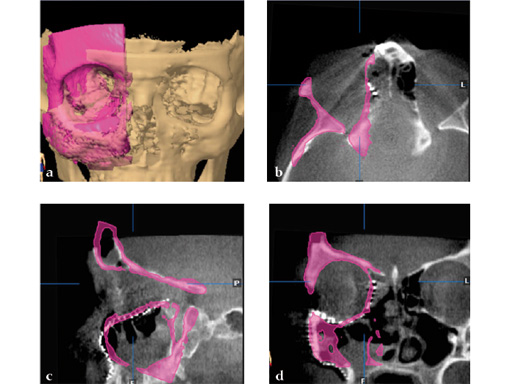

Case 2: A 19-year-old woman had an extended sinunasal carcinoma in the right maxillary sinus area. fig 2 shows four views of the virtual preplanned computer-aided design; the reconstruction is represented in pink (fig 2a). The three remaining multiplanar views show the overlapping images of the virtual preplanned reconstruction (pink) and reconstruction result performed by using two individualized 3-D meshes (one for a three-wall-reconstruction of the orbit and one for reconstructing the right midfacial prominences).